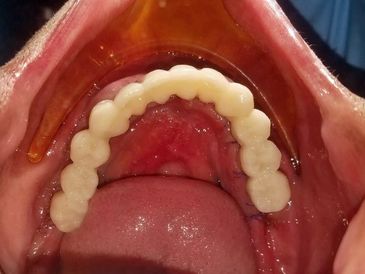

Day Two begins by taking the temporary teeth out of the mill.

Dr. Gibney adds some stain to the grooves of the teeth to make them look more realistic.

Dr. Gibney and the other dentists examine the temporary teeth.

Gerald comes in very early on Day Two. Day Two is always very quick for the patient. The temporary teeth are cemented in and Gerald is on his way!

The temporary teeth will typically remain in the patient's mouth for 4-6 months. They act as a cast to let the implant sites heal.